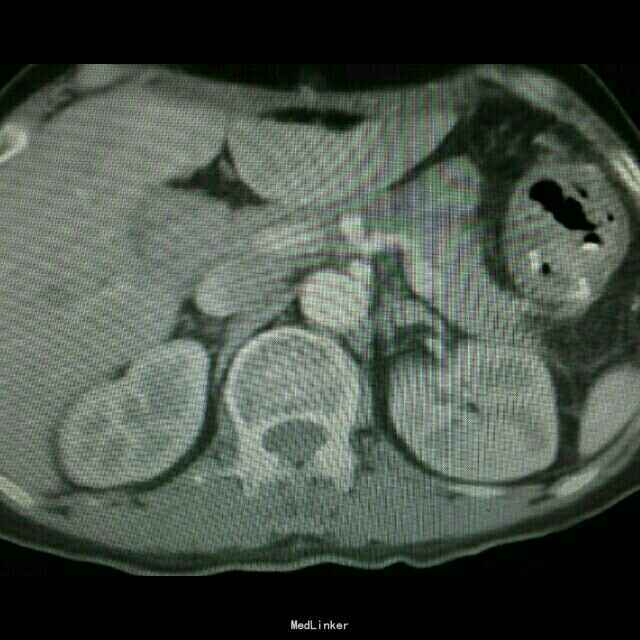

查体:入院后查体腹部平软,未见胃肠型,上腹部正中部可见20cm陈旧性瘢痕,腹部无压痛及跳痛,无肌卫;叩诊鼓音,肝脏及脾脏肋下未及;肝肾区无叩击痛,移动性浊音阴性,肠鸣音弱,1-2次/分。 检查:本次入院后查:WBC:9.2*10^9/L,Na:132mmol/L,余指标基本正常。电子胃镜:胃大部切除术后改变(毕II)吻合口粘膜充血水肿明显,直径约1.2cm,分别尝试进入输入袢及输出袢,见肠腔无明显狭;上腹部增强CT:1胰十二指肠切除术后;2肝脏多发小囊肿;3腹腔内未见明显感染及肿瘤转移征象。上消化道造影:残胃形态、扩张可,未见明显潴留液,蠕动较弱,中远部充盈不佳,胃小肠吻合口宽约1.2cm,未见狭窄及碘水渗漏。胃排空较慢。